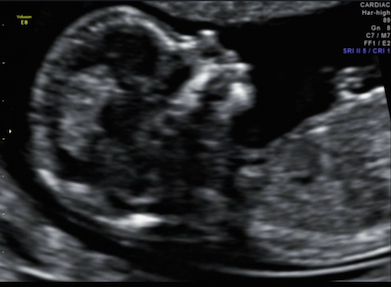

Picture from my 12w5d ultrasound. What's your guess? Thank you Attachment 18952